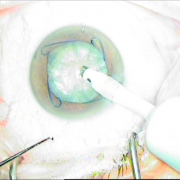

Τραυματική διάσπαση ζίνειου ζώνης 5 ωρών

Τραυματική διάσμαση ζήνειου

ζώνης 5 ωρών

Τοποθέτηση ειδικού δαχτυλίου

Φακοθρυψία

Τοποθέτηση αναδιπλούμενου φακού

Τοποθέτηση αναδιπλούμενου

φακού

Τελικό αποτέλεσμα